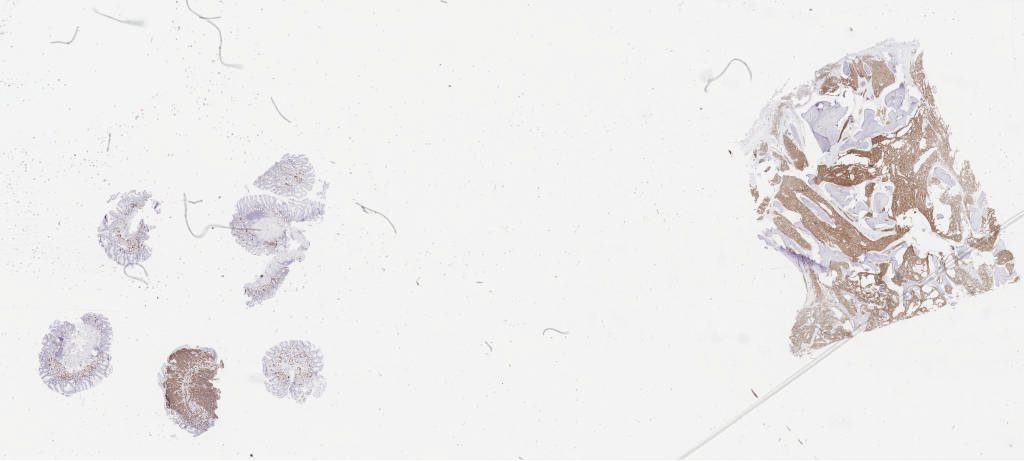

CK AE1 AE3.svs

137448 x 54982

@ 40X